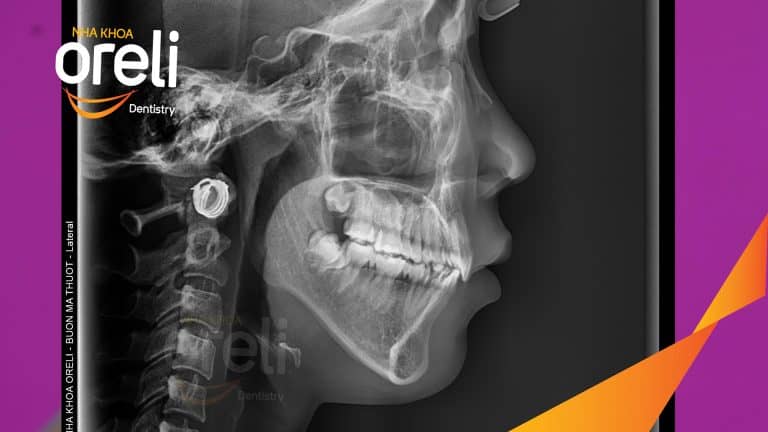

Ca chỉnh hô có nhổ 4 răng 4 thay đổi góc nghiêng đẹp – Kết quả thay đổi sau 3 năm tại nha khoa Oreli Niềng răngHô Xem thêm